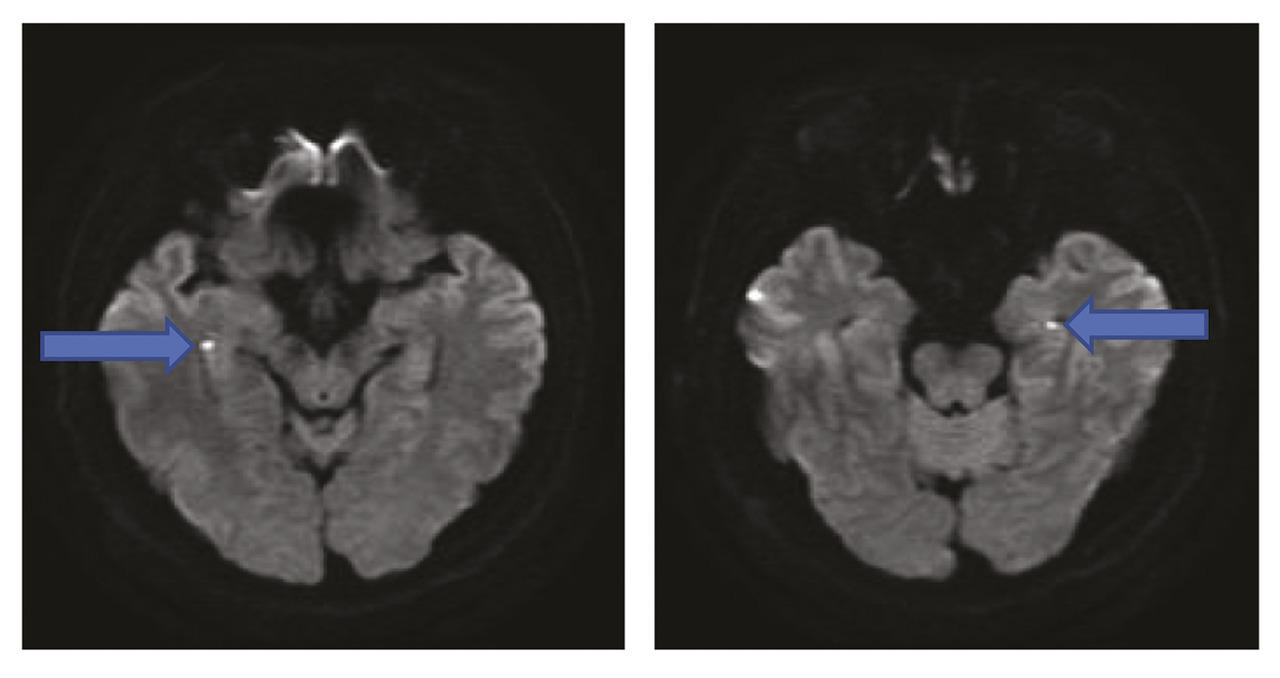

Le diagnostic repose sur les critères figurant dans letableau 1 . La présence d’un témoin du début de l’épisode est capitale, afin d’exclure une amnésie post-traumatique ou post-critique. Le tableau d’abolition aiguë isolée de la mémoire épisodique élimine une confusion mentale, une aphasie, un état psychotique. L’imagerie par résonance magnétique (IRM) exclut un accident vasculaire cérébral et montre parfois à la partie latérale de l’hippocampe (de façon uni- ou bilatérale) des hypersignaux punctiformes en séquence de diffusion et en T27 qui sont reconnus comme la signature de l’IA (figure ) et disparaissent en quelques jours.

L’hypothèse physiopathologique est celle d’un stress métabolique de l’hippocampe. Les hypersignaux en IRM traduisent un œdème cytotoxique, la spectro-IRM montre un pic de lactates de même localisation.8 Une élévation de la cortisolémie souvent constatée va dans le même sens. La cardiopathie de Takotsubo, également liée au stress, parfois décrite en association avec l’IA,9 pourrait expliquer l’élévation de la troponine parfois notée au cours de l’IA.